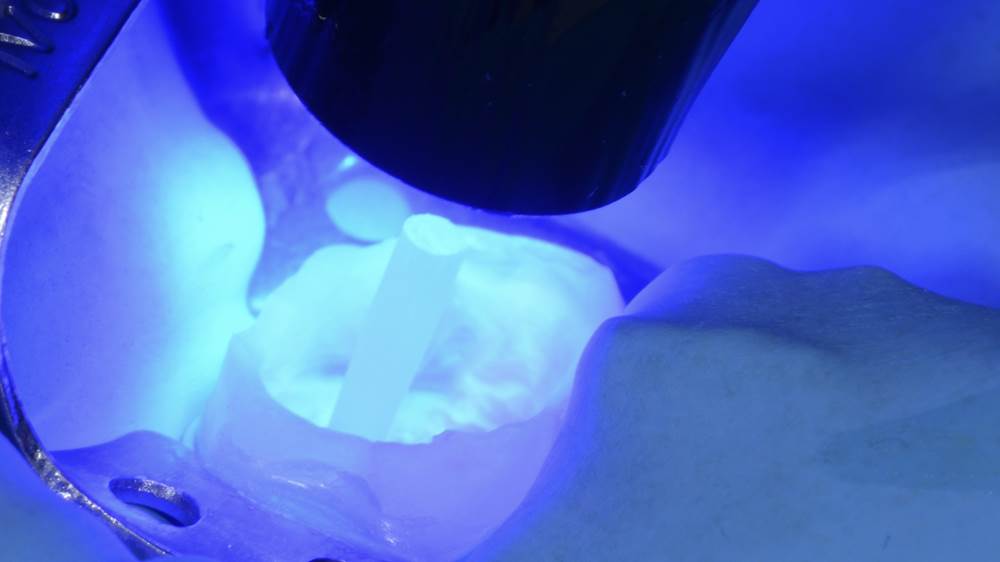

3. Sementtiylimäärän poisto ja valokovetus juurikanavanastan asettamisen jälkeen.

15. Sementtiylimäärän esikovetus.

16. Sementtiylimäärän poistaminen sondilla.